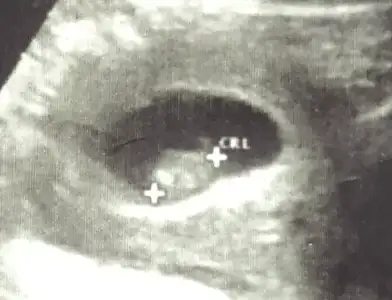

ben de araya kaynasam? daha önce buraya atmıştım ama hiç tahminde bulunan olmadı.ilki 6 hafta ikincisi 7+3.6-7 haftalık ultrason varmı yollar mısın Bi daha bakim merak ettim

doktor bir şey demedi ama.Vajinal ultrason ise erkek karın ultrasonu ise kızben de araya kaynasam? daha önce buraya atmıştım ama hiç tahminde bulunan olmadı.ilki 6 hafta ikincisi 7+3.

cuma günü ikili tarama için gittiğimde görüğüm şey kordon değilse erkek gibiydidoktor bir şey demedi ama.

Kız bence

Kıza benziyor

Bana da yorum yapar mısınKıza benziyor